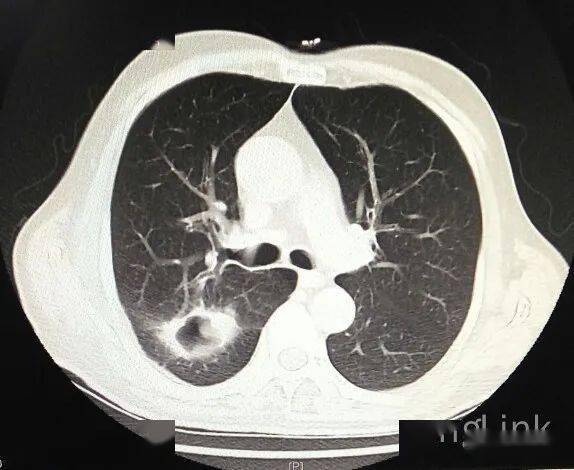

【病例】右肺下叶癌性空洞1例ct影像表现

这个空洞长的太帅了,简直是空洞中的楷模,结核or肺癌?